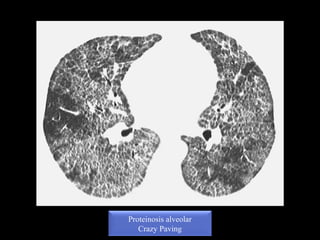

 EMPEDRADO LOCO O CRAZY PAVINGEMPEDRADO LOCO O CRAZY PAVING: Opacidades en vidrio

deslustrado superpuestas a patrón reticular (engrosamiento septal

interlobulillar e intralobulillar)

*Normalmente traduce proceso activo y tratable

*Patología del espacio aéreo, intersticial o ambos

*Se asocia a síntomas agudos o subagudos/crónicos

Dd del patron en empedrado

Proteinosis alveolar

Crazy Paving